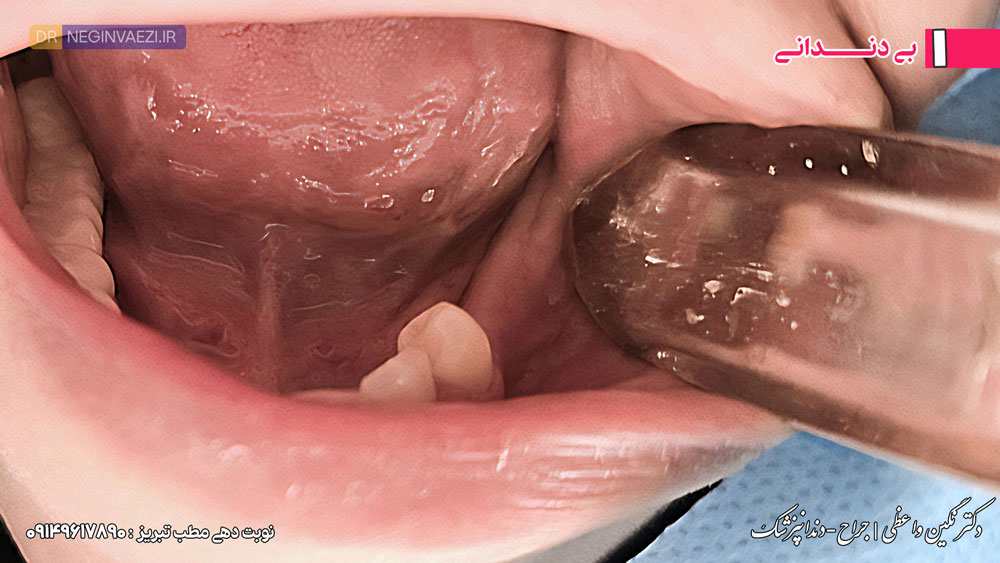

بی دندانی

در مرحله بی دندانی، نبود یک یا چند دندان می تواند علاوه بر کاهش زیبایی لبخند، عملکرد جویدن و اعتماد به نفس فرد را تحت تأثیر قرار دهد. بررسی وضعیت اولیه دهان، پایه ای ترین گام برای برنامه ریزی دقیق درمان ایمپلنت و دستیابی به نتیجه ای موفق است.لذا در این مرحله در ابتدا معاینات لازم از جمله بررسی وضعیت لثه ها، ضخامت استخوان و… صورت میگیرد.